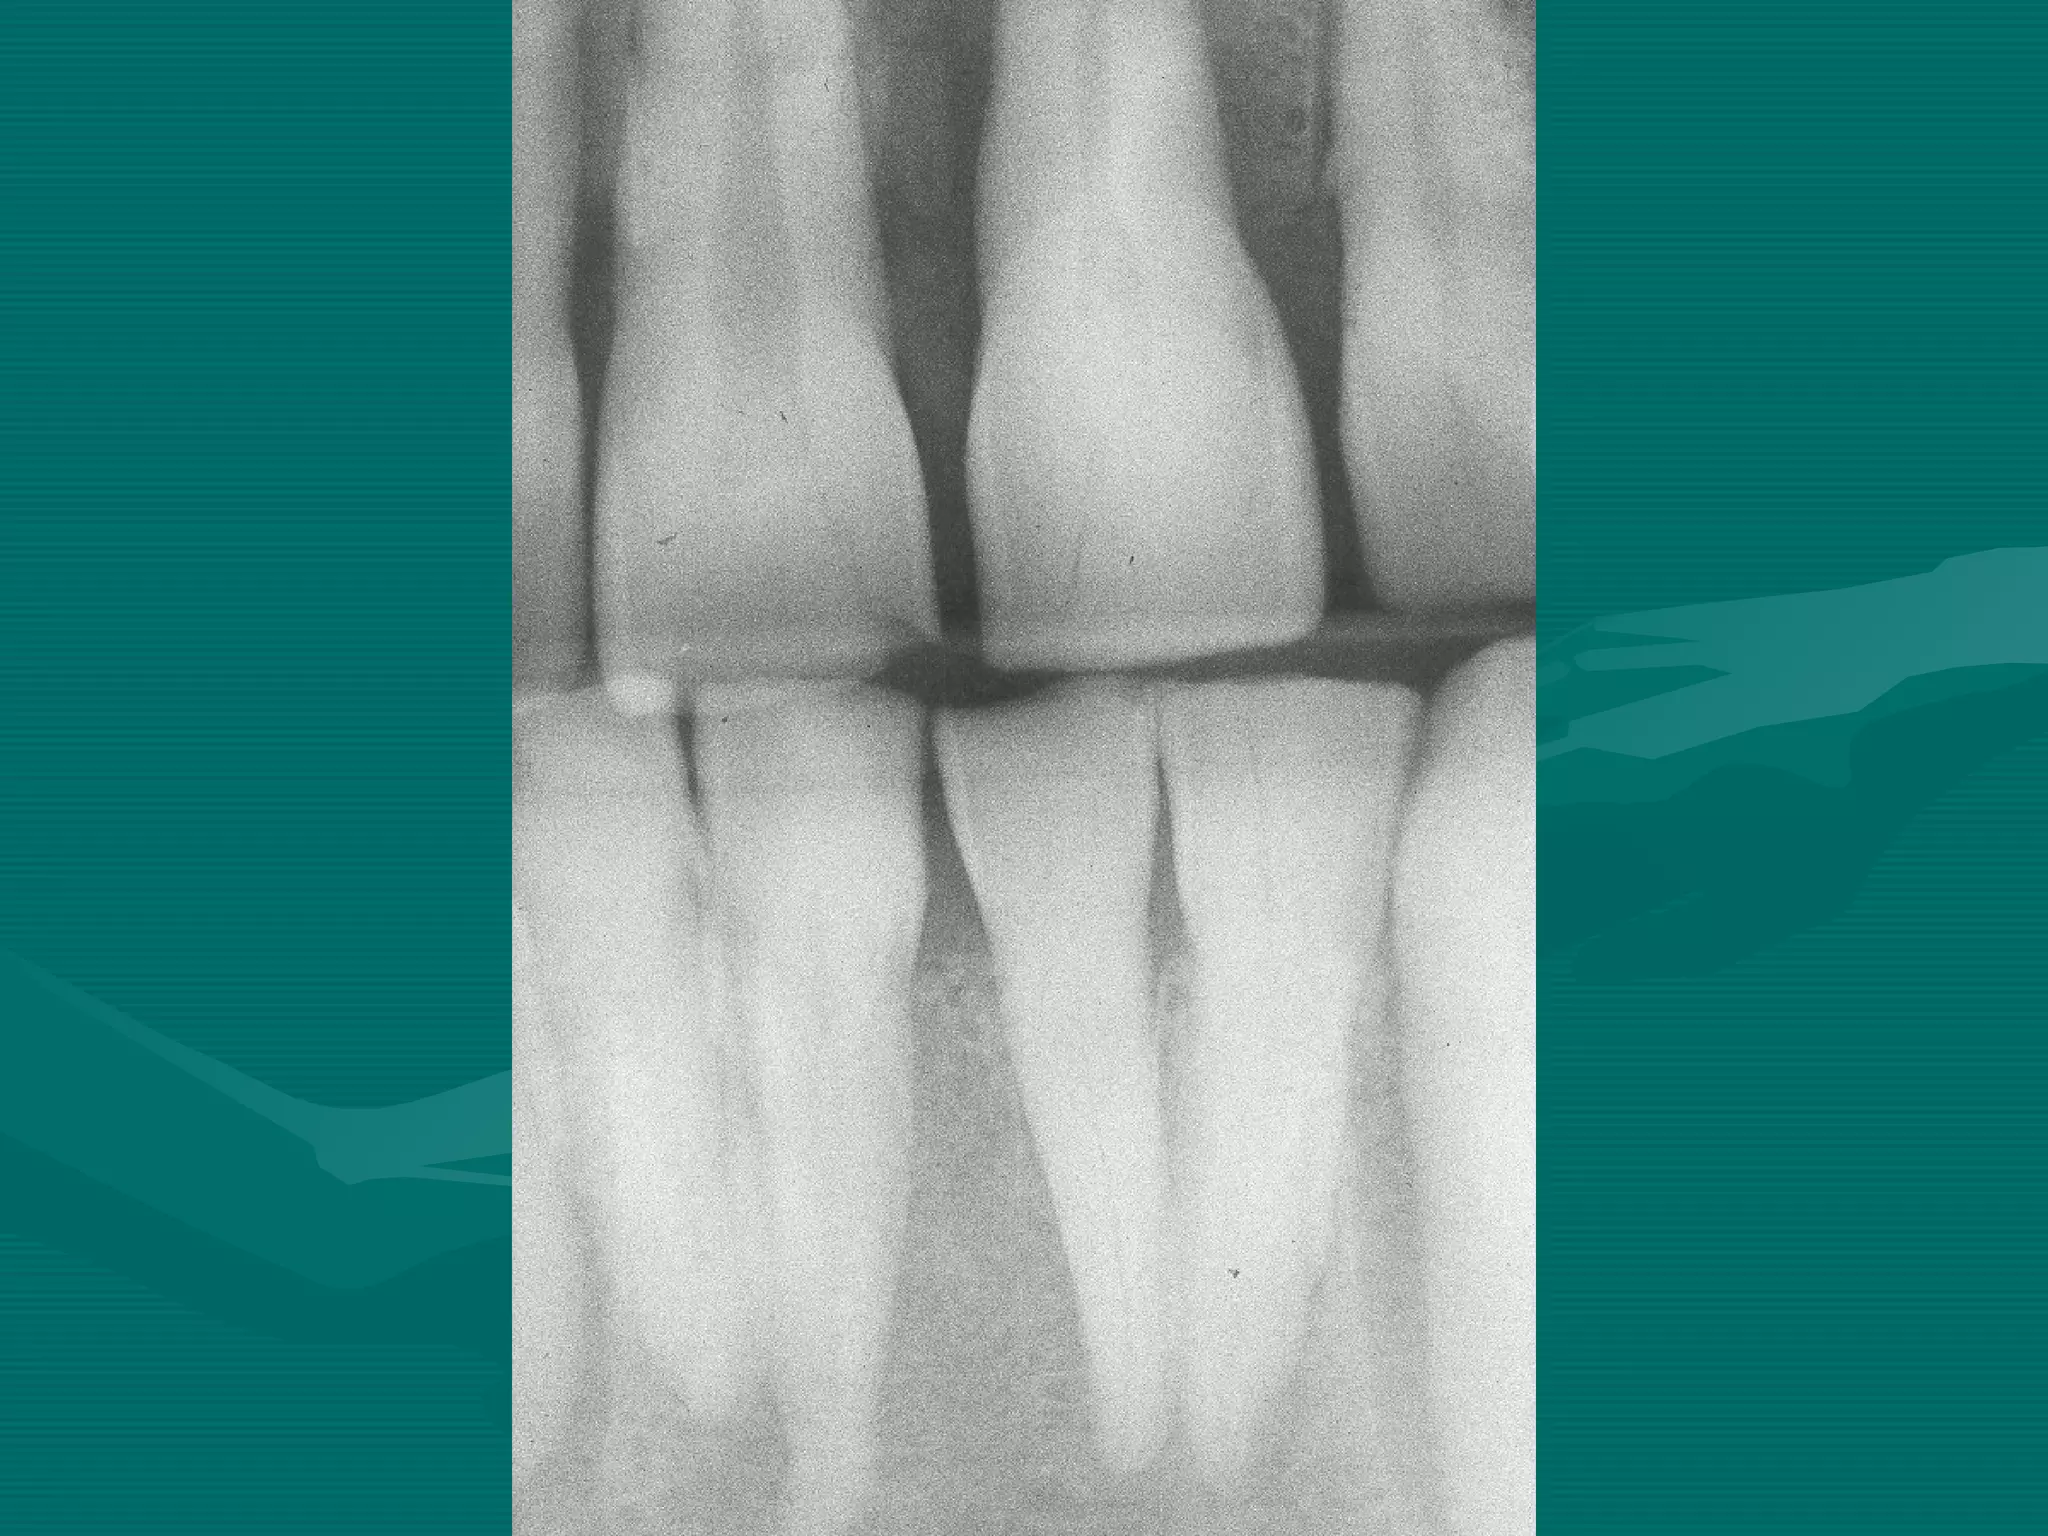

BITEWING

ERRORS

Bite-wing Technique ErrorsBite-wing Technique Errors

Patient is not biting on the bite block

Film placement

Film bending

Horizontal angulation

Single overlap. Technique OK

Cone cut

Film Reverse